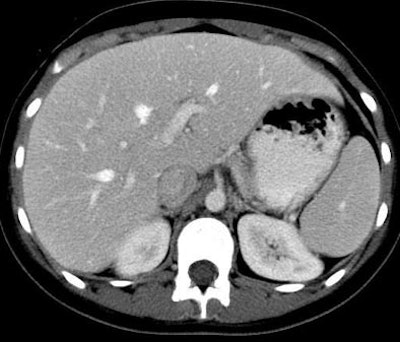

| Patient with fever after prolonged neutropenia. Above, arterial-phase CT of liver shows a type 2b lesion (arrow). Unenhanced CT (below) shows a corresponding hypoattenuating lesion, while portal-venous-phase CT (bottom) shows a tiny nonspecific hypodensity (type 1 lesion). This case demonstrates how arterial-phase CT adds specificity. Although portal-venous phase depicted the lesion, it would be extremely difficult to "call" it an abscess. The enhancement pattern on arterial phase CT makes for a more confident diagnosis. All images courtesy of Dr. Ur Metser. |

![]() |